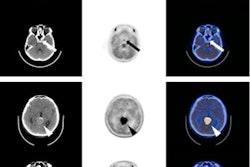

Contrast-enhanced MRI is the gold standard for diagnosis and treatment planning. However, MRI can have limited accuracy in distinguishing recurrence from treatment effect in the postsurgical and postradiation setting. Ga-68 DOTATATE, on the other hand, is a PET radiotracer that targets somatostatin receptor 2 (SSTR2) with high affinity. This attraction is particularly important because SSTR2 is expressed at a high level in meningiomas.

The researchers found Ga-68 DOTATATE PET showed unique uptake patterns for meningiomas, pituitary glands, and post-treatment changes across all subjects. The modality also improved the researchers' ability to visualize the extent of disease and confirm parenchymal and osseous invasion.

As a result, the modality detected 31 unique lesions from the scans, which included 19 confirmed meningiomas (61%) and seven lesions (23%) with low avidity. The latter finding would suggest a change in the disease status of the patient after treatment. The remaining five lesions (16%) could not be definitively diagnosed and were deemed indeterminate.